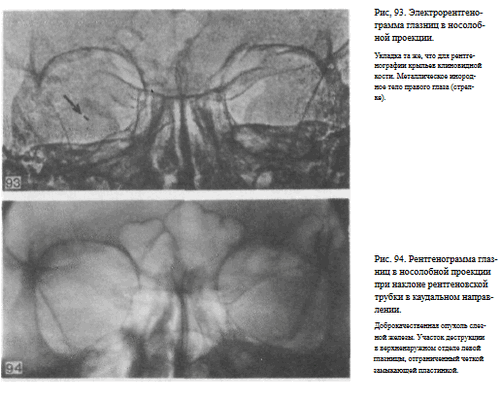

СНИМОК ГЛАЗНИЦЫ В НОСОЛОБНОЙ ПРОЕКЦИИ

Назначение снимка — изучение контуров костей, образующих вход в глазницу, структуры верхней и наружной ее стенок, ширины и контуров верхних глазничных щелей, а также выявление инородных тел в полости глазницы.

Укладка больного для выполнения снимка, информативность снимка, критерии правильности технических условий съемки и правильности укладки те же, что для снимка крыльев клиновидной кости и верхних глазничных щелей.

В качестве примера информативности снимка глазниц в носолобной проекции для выявления инородных тел глаза и деструктивных изменений стенок приводим два наблюдения.

Одно из них — случай ранения глаза металлической стружкой (рис. 93), другое — случай деструкции верхненаружного края глазницы при доброкачественной опухоли слезной железы (рис. 94).